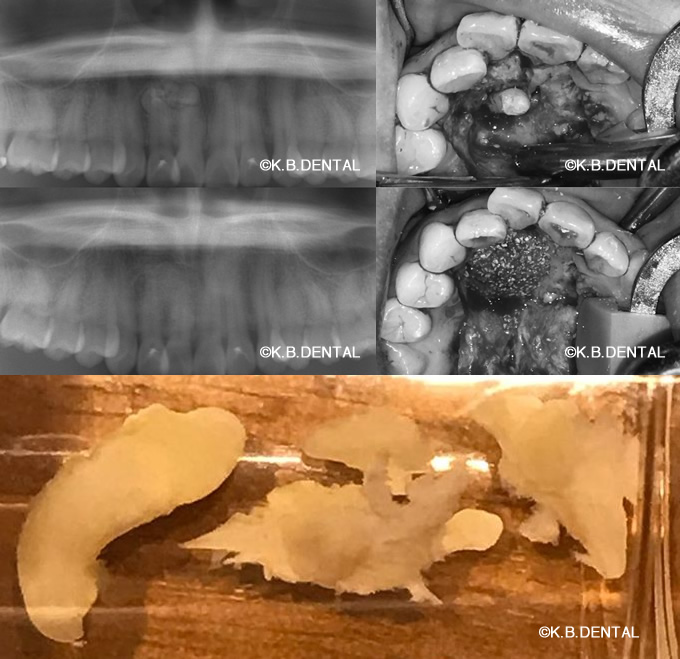

エナメル上皮腫(濾胞型)

術後2年経過の最も典型的なエナメル上皮種です。再発率が非常に高いので最低でも5年以上の経過観察が必要となります。今回は摘出術と一部健常域まで辺縁切除(骨を削る)を行いました。

1枚目(パノラマ)上:術前 下:術後 摘出部分に新生骨を認めます。

2枚目(CT)上:術前 下:術後 摘出部分に新生骨を認めます。

3枚目 左:摘出物の腫瘍本体と割断像 右:割断して内容物が充実性である事がわかります。

4枚目 上:高倍率 下:低倍率 腫瘍実質の胞巣が濾胞状を示しているのがわかります。